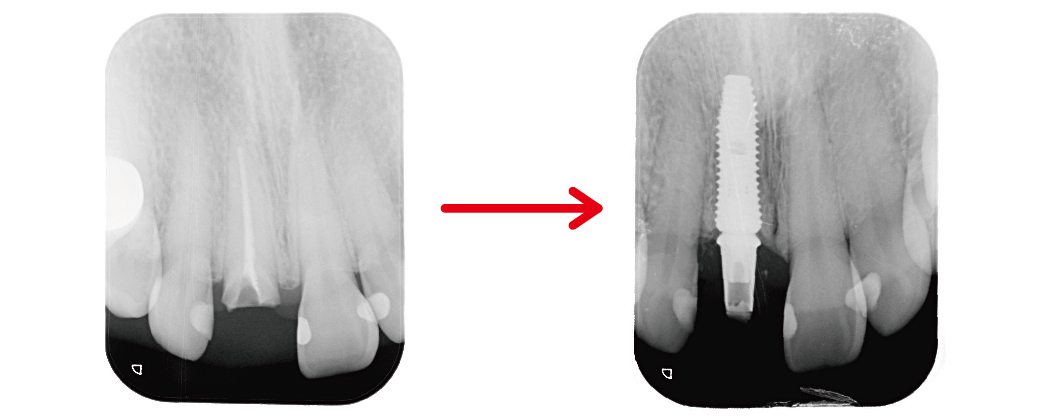

▲從局部X光片紀錄中可以看出拔牙當下,立即植入人工牙根